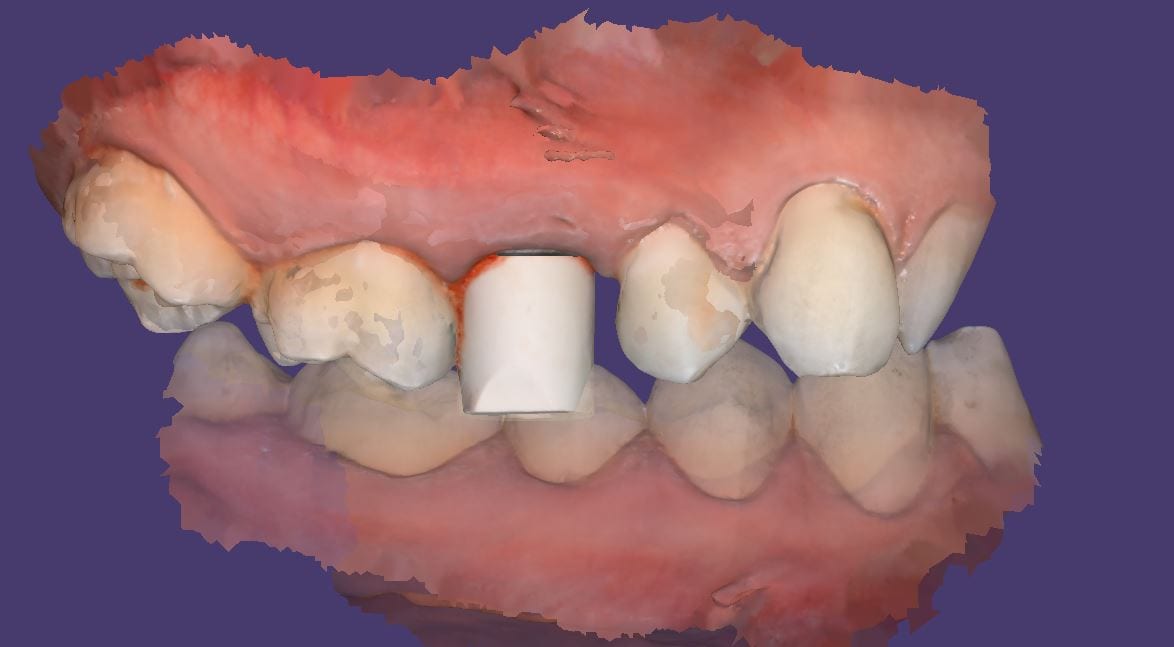

You can scam the opposing (here the upper hybrid was being repaired as the left central incisor had fallen off), scan the denture in place of the appropriate arch, and then you can take the buccal bite.